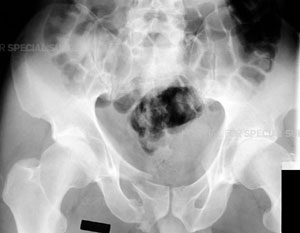

Radiograph of the pelvis demonstrating a fracture of the pubic bone

Radiograph of the left hip demonstrating a posterior dislocation of the hip with an associated

Posterior Wall type fracture of the acetabulum